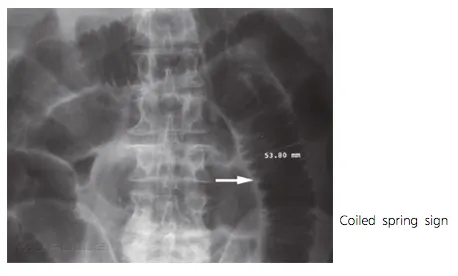

(6) Lymphoma : Intussception (leading point 역할을 함)

D2. Imaging

(1) Simple film : Abd S/E, Chest PA, Lat. decubitus (greatest volue : free air detection)